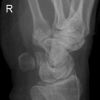

Handgelenk a.p.

1. Möglichkeit:

Frage nach Bandruptur: gewinkelter Vorderarm liegt flach auf dem Tisch, Handgelenk liegt mit der volarer Seite auf der Kassette, D3 verläuft gestreckt in Richtung Radius.

2. Möglichkeit:

Frage Fraktur: Finger locker gebeugt, Hand nach lat. abduziert (abgespreizt).

Zentralstrahl

Senkrecht auf Objektmitte und Filmmitte.

Anmerkung

Darstellung der Handwurzel- und Unterarmknochen, bei Fragestellung von Epiphysenlösung, Grünholz- oder Os scaphoideumfraktur. Zur Beurteilung der Knochenkerne bei Kindern werden Vergleichsaufnahmen notwendig, bei Verdacht auf Subluxation des Os Lunatums, Zusatzaufnahme in Flextion und Reflextion der Hand notwendig (siehe Stressaufnahme).

Qualitätskriterien

Vollständige Abbildung der Metacarpalia, Handwurzelknochen und distaler Unterarm.